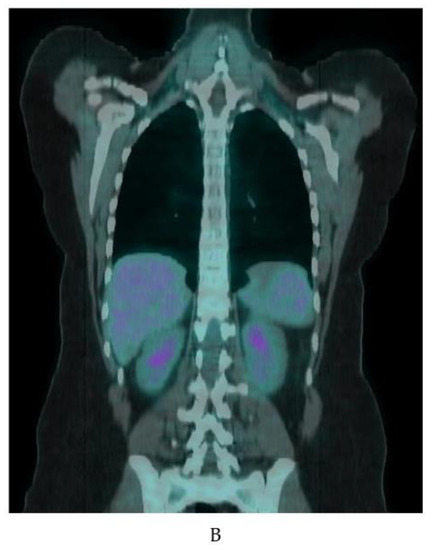

BAT is detected with other clinical and investigational radiotracers. 123I-metaiodobenzylguanidine (MIBG) SPECT/CT localizes sympathetic innervation by using a labeled norepinephrine analogue [75]. MIBG localizes BAT with similar sensitivity to FDG-PET/CT but is less temperature dependent [9,75,76]. The 11C PET tracer and norepinephrine analog 11C-meta-hydroxyephedrin has demonstrated sensitivity to BAT at thermoneutral conditions and its activity correlates with FDG uptake with acute cold in humans [77]. The commonly used SPECT/CT tracer 99mTc-methoxyisobutylisonitrile (MIBI), which localizes to tissues with high mitochondrial density, detects BAT in a non-temperature dependent manner as shown in an example from our clinical practice (Figure 9) [76,78]. 15O-labeled water PET/CT has been used in this setting to measure blood flow, which provides data to estimate tissue-specific metabolic rate using arterial oxygenation and known oxygen extraction fractions [77]. Din and colleagues combined 15O-labeled water PET/CT with inhaled 15O administration to directly measure tissue metabolic rate in humans [79]. The short (2 min) half-life of 15O allows for repeat PET scanning with another tracer on the same day [77,79]. Investigational radiotracer currently include the mitochondrial outer membrane translocator protein, visualized with 18F-FEPPA PET/CT and 11C-PBR28 PET/CT, the cannabinoid type 1 receptor, visualized with 18F-FMPEP-d2 PET/CT [80,81,82,83], and PD-L1, visualized with radiolabeled antibodies [84,85].

Figure 9.

99mTc-MIBI uptake in iBAT on a clinical scan. Supraclavicular BAT uptake shown coronal and axial fused 99mTc-MIBI-SPECT/CT (yellow arrows). Salivary gland uptake (white arrows) is normal.